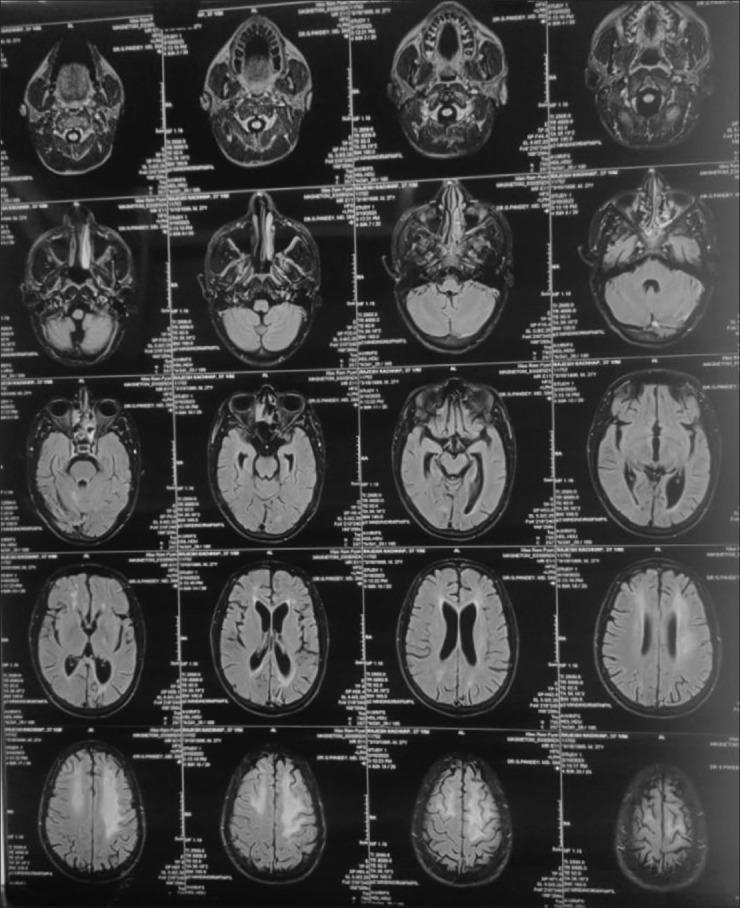

Subacute sclerosing panencephalitis (SSPE), slowly progressive neurological disorder, commonly affects children who had past history of measles or if their parents forgot to provide measles vaccination. All cases with simultaneous psychiatric and neurological features with progressive deterioration of intellectual functioning were evaluated with routine blood investigations, magnetic resonance imaging, electroencephalography (EEG), cerebrospinal fluid (CSF) examination, and so on, to rule out mimics. The cases meeting the diagnostic criteria of SSPE are analyzed retrospectively. The clinician should consider SSPE in cases with comorbid neurological and psychiatric features after excluding the common causes, and neuroimaging, EEG, and CSF study are must.

亚急性硬化性全脑炎(SSPE)是一种缓慢进展的神经系统疾病,通常影响有麻疹病史或父母忘记为其接种麻疹疫苗的儿童。对所有具有精神和神经症状且智力功能逐渐恶化的病例进行了常规血液检查、磁共振成像、脑电图(EEG)、脑脊液(CSF)检查等评估,以排除类似疾病。对符合SSPE诊断标准的病例进行回顾性分析。临床医生在排除常见病因后,对于伴有神经和精神合并症的病例应考虑SSPE,神经影像学、EEG和CSF检查是必需的。